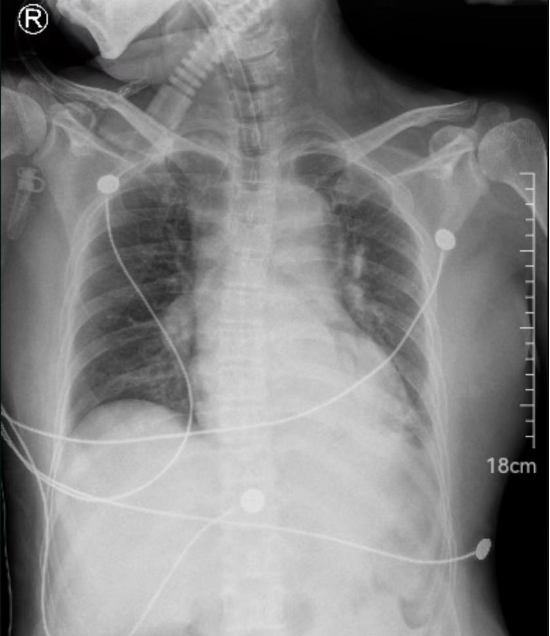

胸部影像学表现: 两肺纹理增多、紊乱,两肺可见较多斑片状模糊影,肺门、纵膈未见增宽。心影增大,心胸比约0.59,主动脉弓可见钙化灶。右膈未见异常,左膈及肋膈角模糊。气管见置管影。(见图1)

图1 2023-10-24 DR检查